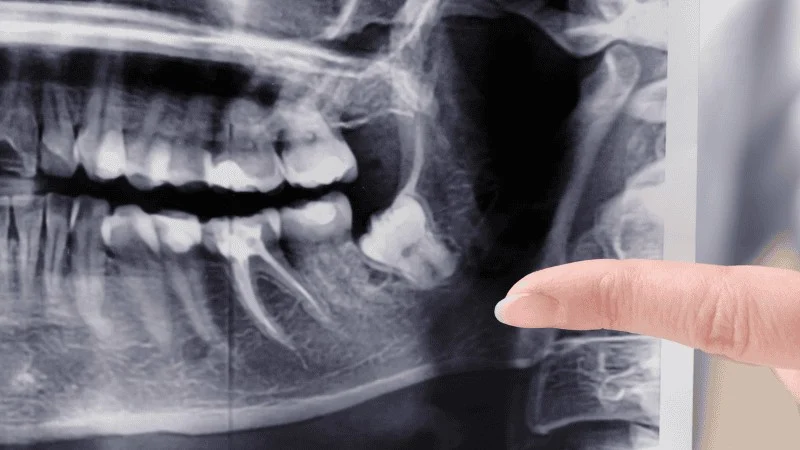

You may still qualify for dental implants with bone loss if you have enough healthy jawbone to hold the implant. Your dentist will use X-rays or a 3D scan to measure bone height and width.

These images show whether your jaw can support stable osseointegration, which is when the implant bonds to the bone.

Your dentist checks bone levels with X-rays or 3D scans. If bone is limited, treatments such as grafting can rebuild support. Many clinics explain how dental implants with bone loss can still work with the right plan.

Your dentist starts with digital X-rays to check bone height and spot problem areas. These images show missing teeth, bone shrinkage, and signs of gum disease.

For a deeper view, you may need a CT scan. A 3D scan measures jawbone density, width, and height in exact millimeters. It also shows nerves and sinuses, which helps prevent injury during surgery.